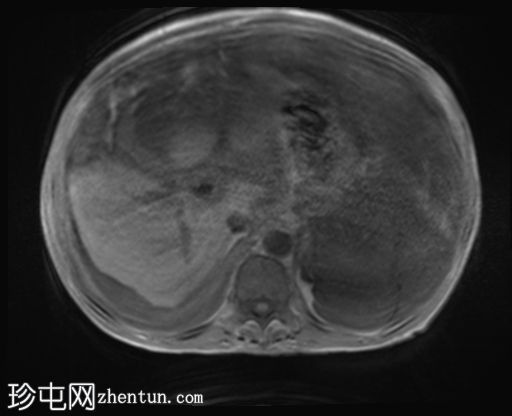

冠状位

T2

升结肠壁增厚,尤其前壁,形成肿块,T2信号高,提示其为黏液性肿块。肿块无扩散受限,增强扫描后几乎无强化。

腹腔内可见大量T2信号高、T1信号低至中等的包裹性积液,与腹膜凹陷相符,并导致内脏表面(尤其是肝脏和脾脏)呈扇贝状。这些表现是腹膜假黏液瘤的特征性表现,可能由黏液性肿瘤播散引起。